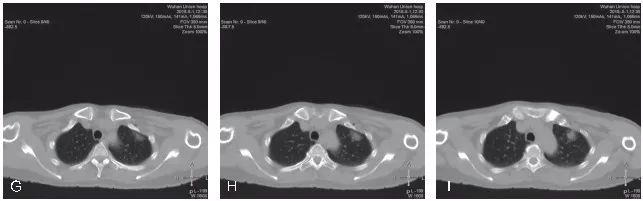

图5-3 展示了1例pGGO的CT引导下经皮穿刺活检

A~C. 显示患者左肺上叶前段胸膜下pGGO,选取仰卧位进行穿刺活检;D~F. 显示穿刺活检的实时CT影像;G~I. 显示活检完成后,拔除同轴穿刺针,再次进行CT扫描,未见明显气胸及肺内出血征象。病理结果示:(左肺)浸润性腺癌